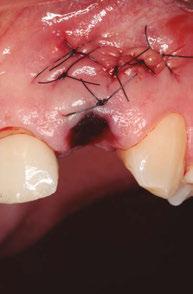

–Implante inmediato en incisivo lateral superior con técnica de «Socket Shield» y acceso vestibular para legrado de la lesión periapical, por el Dr. Ignacio Tormo Jiménez y cols. [106]